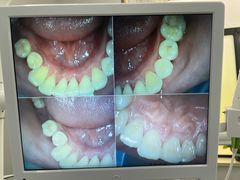

• 牙博士口腔品牌连锁(杨浦店)

• -牙博士口腔品牌连锁(杨浦店)

DonBilly | 22-06-06